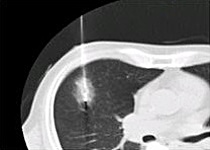

腺がんは初期の病変ではすりガラス状陰影(Ground Glass Attenuation : GGA)であることが多く、胸部レントゲン検査では発見が非常に難しく、高分解能CT(HRCT)が有用です(左図)。

扁平上皮がんは比較的太い気道(気管支)に発生することが多いがんで、比較的頻度が高く、肺がん全体の25〜30%を占めます。扁平上皮がんの主な原因は喫煙と考えられており、たばこの本数が多ければ多いほど、危険性は増加します(中図)。

小細胞がんは非小細胞がんに比べて、発育が速く転移を起こしやすいことと、抗がん剤や放射線療法が非常に有効なことが特徴で、この点で他の肺がんとは治療上の対応が異なり、手術よりも抗がん剤の治療が主体になることの多い肺がんです(右図)。